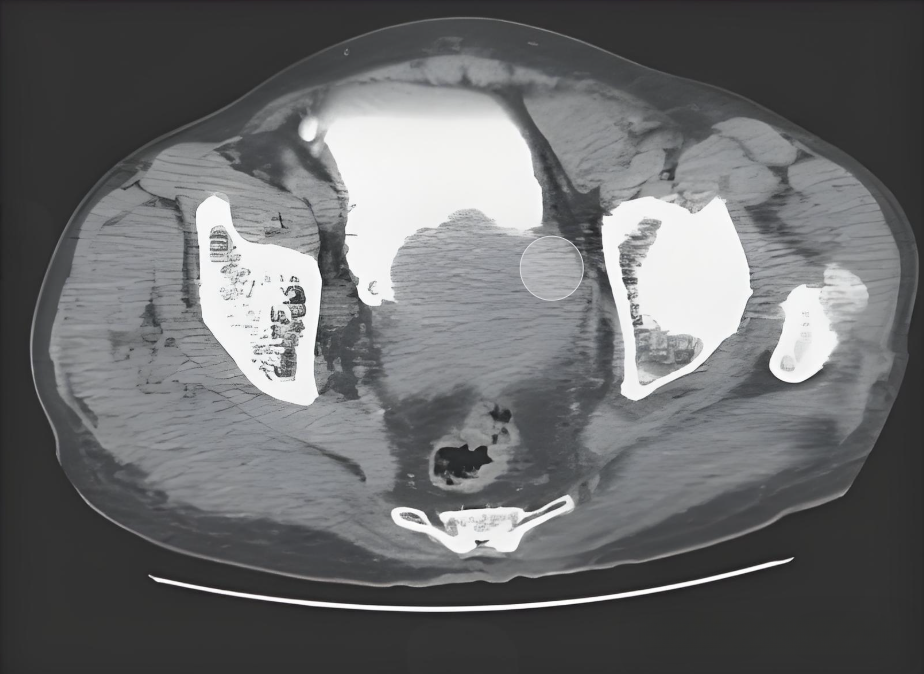

前列腺癌作为男性常见的恶性肿瘤,其早期诊断对于提高生存率至关重要。医学影像技术在此过程中发挥着关键作用,其中前列腺图像的分割更是图像处理中的核心环节,具有深远的意义。

在前列腺放射治疗的过程中,精确分割前列腺图像是首要步骤。通过CT图像分割,医生能够准确界定前列腺的位置和边界,为制定放疗计划提供坚实的依据。同时,精确分割还能确保放疗剂量精准地作用于肿瘤区域,最大程度地保护周围正常组织免受损伤。

此外,新型影像技术如超声弹性成像、MRI和PET-CT在前列腺肿瘤诊断中的应用日益广泛。这些技术提供了更为精确的诊断信息,助力医生制定更为科学合理的治疗方案。而前列腺CT图像分割作为其中的重要一环,其重要性愈发凸显。